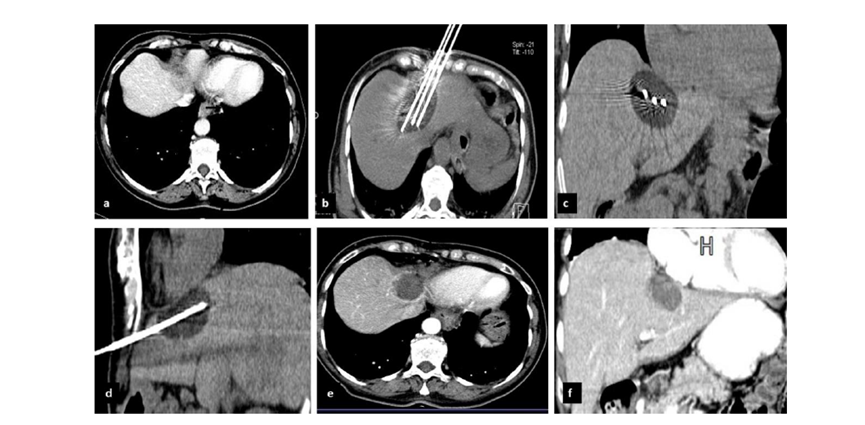

62歲女性,肝轉(zhuǎn)移(卵巢癌)腫瘤的完全消融病例(a)軸向CT顯示病變位置毗鄰心臟和上腔靜脈(黑色箭頭)。(b)術(shù)中軸向CT掃描:使用三個(gè)冷凍探針。1個(gè)月后的軸向(e)和冠狀位(f)增強(qiáng)CT掃描顯示低密度區(qū)域,由于肉芽組織反應(yīng)引起的邊緣增強(qiáng)。

技術(shù)成功100%,92% 的病灶中觀察到腫瘤完全消融。16 名患者 (33%) 出現(xiàn)局部復(fù)發(fā)。10 名患者 (20%) 因局部復(fù)發(fā)或腫瘤消融不完全而接受二次冷凍消融術(shù)。

7名患者出現(xiàn)輕微并發(fā)癥,未發(fā)現(xiàn)膿腫形成、膽漏、膽汁瘤或血液學(xué)變化。冷凍消融可安全、有效治療毗鄰重要臟器的原發(fā)性肝臟腫瘤和肝轉(zhuǎn)移瘤患者,有效控制腫瘤局部進(jìn)展,使患者生存獲益。我國作為肝癌大國,對于肝癌的治療一直給予高度重視?;趯<夜沧R和相關(guān)文獻(xiàn)研究結(jié)果顯示,冷凍消融技術(shù)具有高效、低成本、創(chuàng)傷小、適應(yīng)證廣、并發(fā)癥相對較少等優(yōu)點(diǎn),可有效延長患者生存期、提高生活質(zhì)量、降低患者經(jīng)濟(jì)負(fù)擔(dān)。因此,冷凍消融技術(shù)在肝癌的應(yīng)用中有著極高的潛力和廣泛的發(fā)展空間。